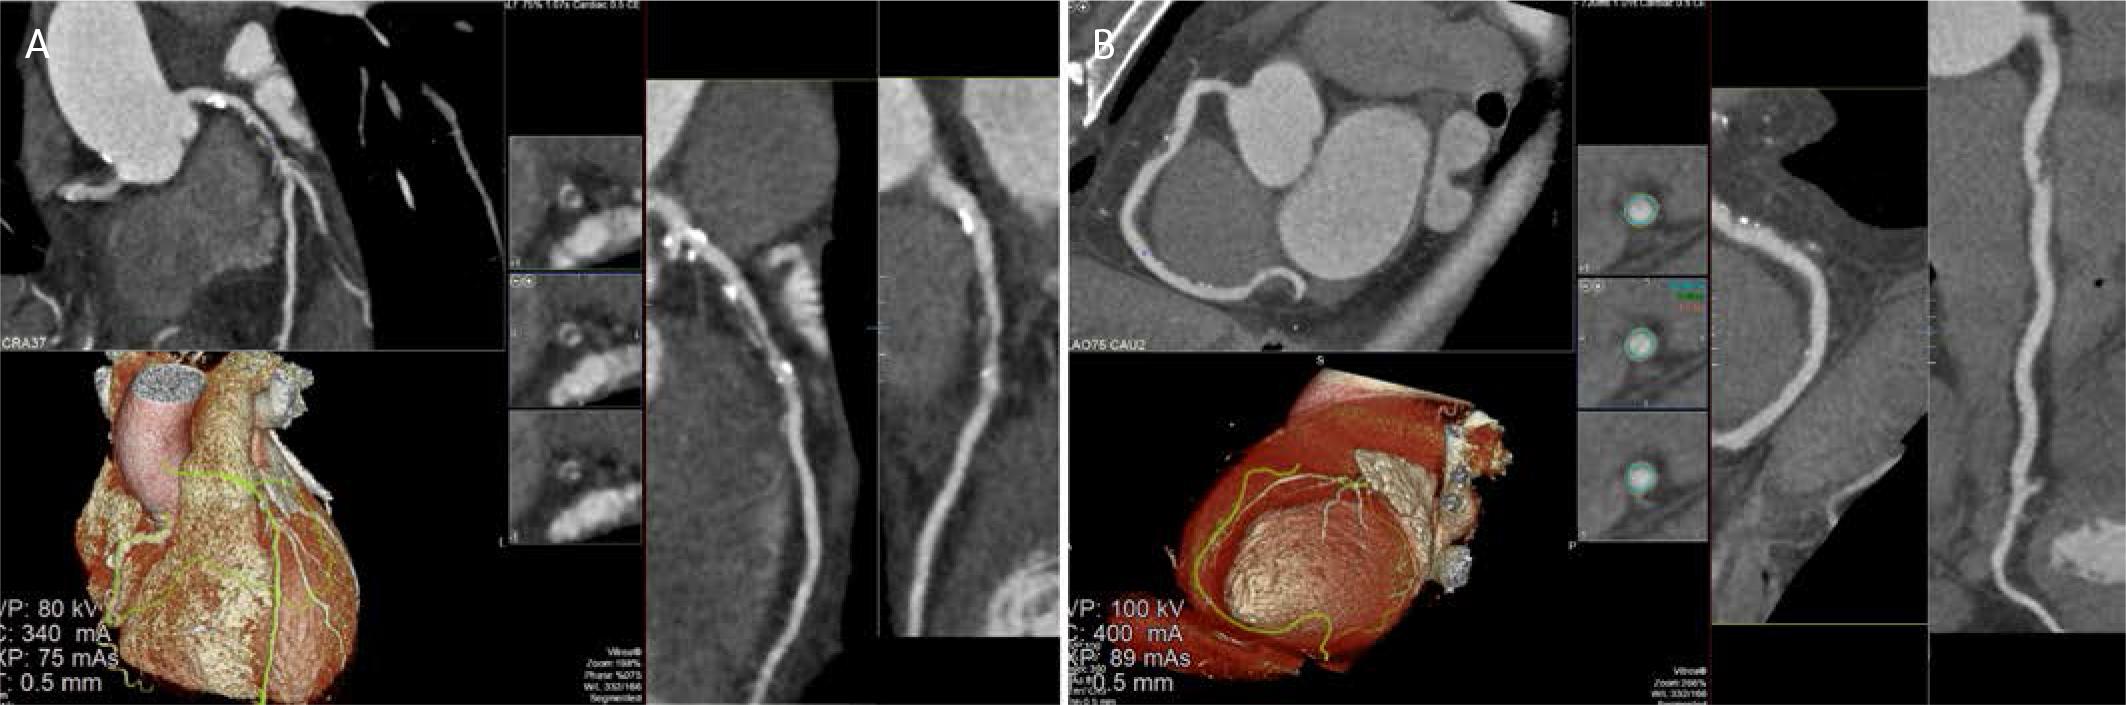

Advanced plaque characterization with CCTA has shifted from a largely qualitative description of ‘high-risk’ features to a more quantitative assessment of plaque composition and pericoronary inflammation. High-risk plaque characteristics, including positive remodeling, the napkin-ring sign, spotty calcification, and low-attenuation plaque, have been independently validated as markers of plaque vulnerability (Figure 1).36 The SCOT-HEART study established low-attenuation noncalcified plaque as an independent predictor of myocardial infarction, while RAPID-CTCA confirmed that low-attenuation plaque burden predicts 1-year adverse outcomes in patients with suspected ACS. However, key evidence gaps remain: (i) the absence of standardized composite scoring systems specifically validated in acute settings, and (ii) the lack of prospective randomized evidence showing that identification of these features changes management and improves outcomes. Most studies have relied on binary or simple additive approaches, and quantitative/composite scores combining low-attenuation plaque, positive remodeling, napkin-ring sign, and spotty calcification are not yet validated for routine clinical use.37,38 Coronary Artery Disease-Reporting and Data System (CAD-RADS) 2.0 incorporates these plaque characteristics, but prospective validation and real-world applicability in acute scenarios remain limited.

CCTA demonstrating high-risk atherosclerotic plaque morphology in the left anterior descending and right coronary arteries. A. Multiplanar reconstruction of the left anterior descending artery demonstrates an eccentric, predominantly non calcified, low attenuation plaque in the proximal–mid segment, associated with positive vessel remodeling and superimposed spotty calcifications. Volume rendered 3D reconstruction confirms the extent and distribution of the lesion along the LAD. B. CCTA images illustrating high-risk plaque characteristics. Axial cross-sectional images (upper right) demonstrate the typical features of vulnerable plaque, including the napkin-ring sign, spotty calcification, and low-attenuation plaque. The 3D volume rendered reconstruction (lower left) depicts the spatial relationship of the high-risk plaque within the coronary anatomy.